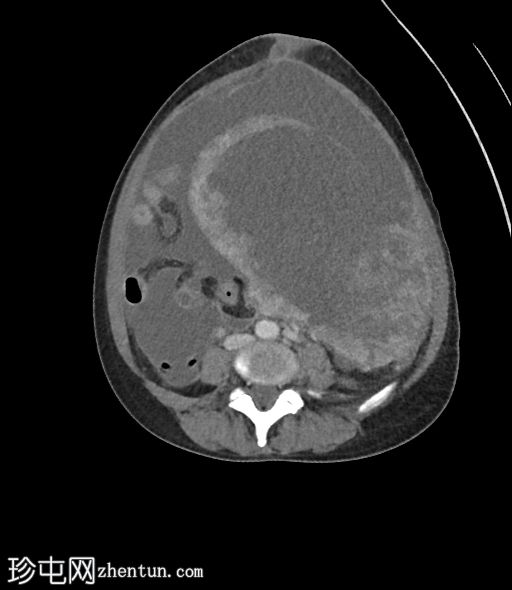

矢状位T1加权像

增强脂肪抑制像

4.jpg

增强扫描图像显示,与其他肌瘤相比,该病灶呈异质性强化,强化区域混杂,中心大片区域无强化(与T2加权像上的囊性区域相对应)。

在原有肌瘤内快速生长出一个体积较大、异质性且伴有囊性/坏死区域的病灶,高度怀疑为子宫平滑肌肉瘤。